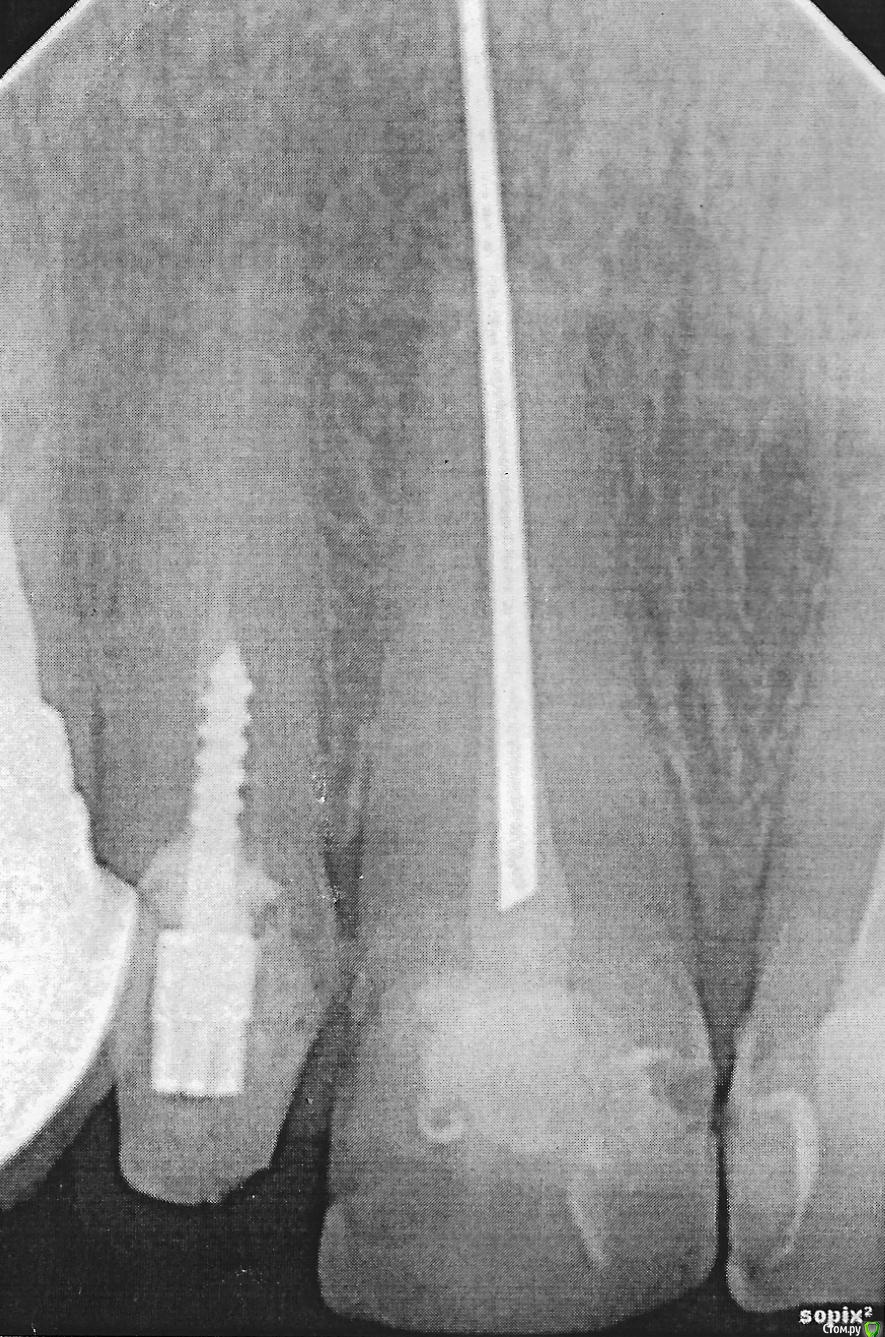

Наталия1966 Опубликовано 1 октября, 2019 Поделиться Опубликовано 1 октября, 2019 (изменено) Лет 30 назад запломбировали зуб. Проблем не было. Теперь встал вопрос о протезировании и вот такая полоса белая в корне. Что это может быть и можно ли в нее ввернуть штифт Изменено 1 октября, 2019 пользователем Наталия1966 Ссылка на комментарий

red_butler Опубликовано 1 октября, 2019 Поделиться Опубликовано 1 октября, 2019 Это серебряный штифт, его можно удалить 1 Ссылка на комментарий

Наталия1966 Опубликовано 2 октября, 2019 Автор Поделиться Опубликовано 2 октября, 2019 Можно ли в этот зуб ввернуть новый штифт не удаляя старого, ведь, штифт изогнут, значит материал достаточно мягок Ссылка на комментарий

DmitrySH Опубликовано 2 октября, 2019 Поделиться Опубликовано 2 октября, 2019 Если мы говорим про центральный резец, то лучше достать под контролем микроскопа Ссылка на комментарий

Наталия1966 Опубликовано 2 октября, 2019 Автор Поделиться Опубликовано 2 октября, 2019 (изменено) Если мы говорим про центральный резец, то лучше достать под контролем микроскопаА ввернуть в него? Там все нормально в корне. Просто сверлом его урезать вниз, отчекрыжить кусок и в это пространство ввинтить новый штифт на резьбе. Изменено 2 октября, 2019 пользователем Наталия1966 Ссылка на комментарий

DmitrySH Опубликовано 2 октября, 2019 Поделиться Опубликовано 2 октября, 2019 , не загубят ли мне зуб А ввернуть в него? Там все нормально в корне. Просто сверлом его урезать вниз, отчекрыжить кусок и в это пространство ввинтить новый штифт на резьбе. Это идеальный вариант окончательно загубить зуб Ссылка на комментарий